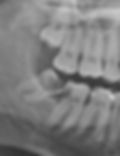

Often, an impacted wisdom tooth is tilted from the straight up and down position characteristic of all the other teeth. Depending on the angle of the wisdom tooth and its proximity to the second molar, the wisdom tooth can cause resorption of the root of the second molar. Sometimes it can also be the secondary cause of decay.